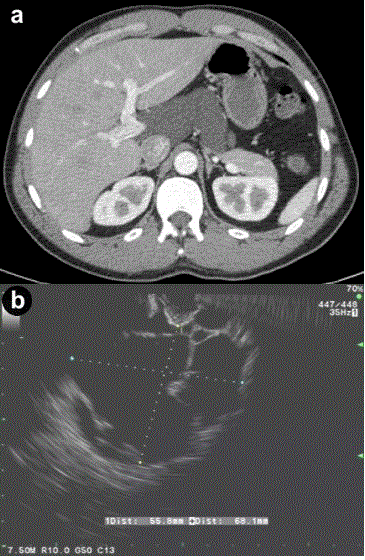

| Figure 2. a. Contrast enhanced abdominal CT scan showing a cystic lesion adjacent to the body of the pancreas and extending into the porta hepatis from Case #2. b. Linear EUS image showing the anechoic cyst with several thin septae from the same patient. |